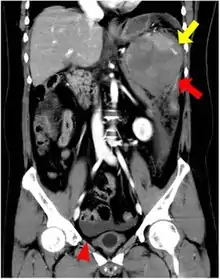

An accessory spleen is a small nodule of splenic tissue found apart from the main body of the spleen. Accessory spleens are found in approximately 10 percent of the population[1] and are typically around 1 centimetre in diameter. They may resemble a lymph node or a small spleen. They form either by the result of developmental anomalies or trauma.[2] They are medically significant in that they may result in interpretation errors in diagnostic imaging[2] or continued symptoms after therapeutic splenectomy.[1] Polysplenia is the presence of multiple accessory spleens rather than one normal spleen.

| CT scan of an accessory spleen (in center of image) between the spleen and left kidney. | |

If splenectomy is performed for conditions in which blood cells are sequestered in the spleen, failure to remove accessory spleens may result in the failure of the condition to resolve.[1] During medical imaging, accessory spleens may be confused for enlarged lymph nodes or neoplastic growth in the tail of the pancreas,[5] gastrointestinal tract, adrenal glands or gonads.[2]